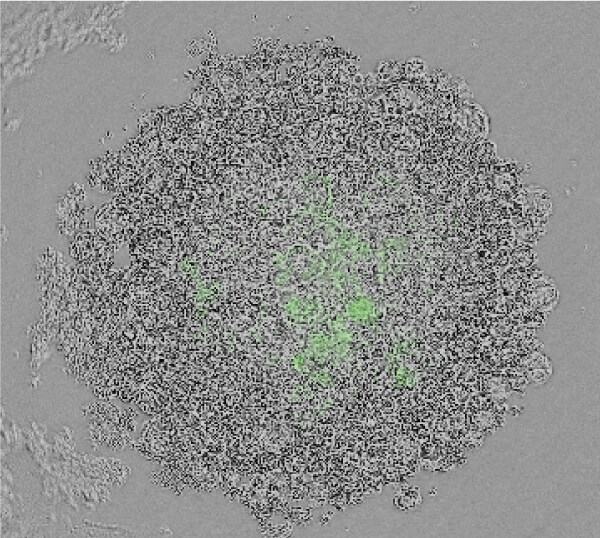

3D解析を用いた形態的定量解析

- 青…DAPI(核を染色)

緑…Ki67(増殖細胞のマーカ) - 形態情報(細胞数、容積、Ki67陽性細胞数)を算出

- 細胞塊あたりの細胞数、細胞密度、増殖細胞の比率が算出することができる。

- F-PDO®の種類により、細胞塊の大きさ、細胞密度、増殖細胞の比率はさまざまである。

| 肺がん | ||

|---|---|---|

| RLUN5 | RLUN16 | RLUN21 |

![]() |